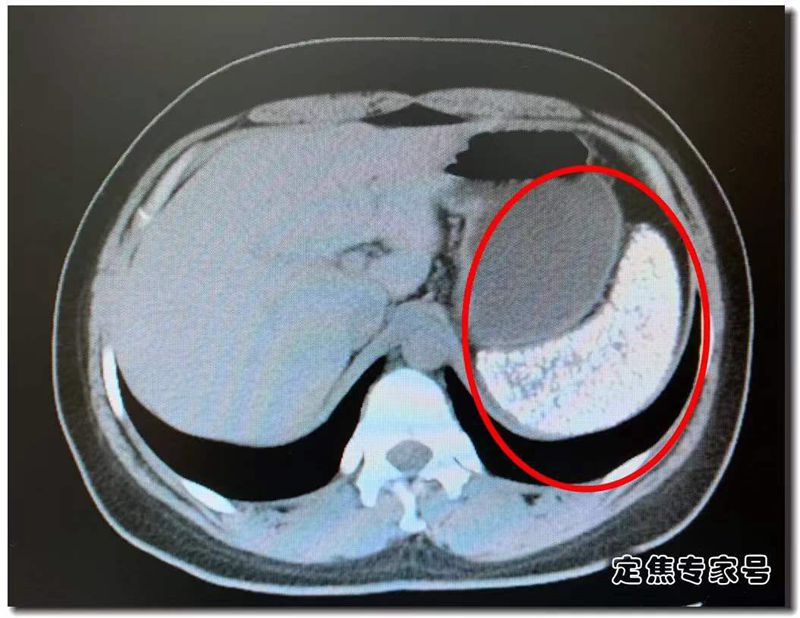

这就是何莉莉的CT片。图中发白的就是她的脾脏。我们知道CT成像,空心的是黑色的,完全实心的白色的。何莉莉的脾脏完全白色,也就意味着她的脾脏已经是一个实心大疙瘩,里面都是钙化点,几乎就是一块板砖了。